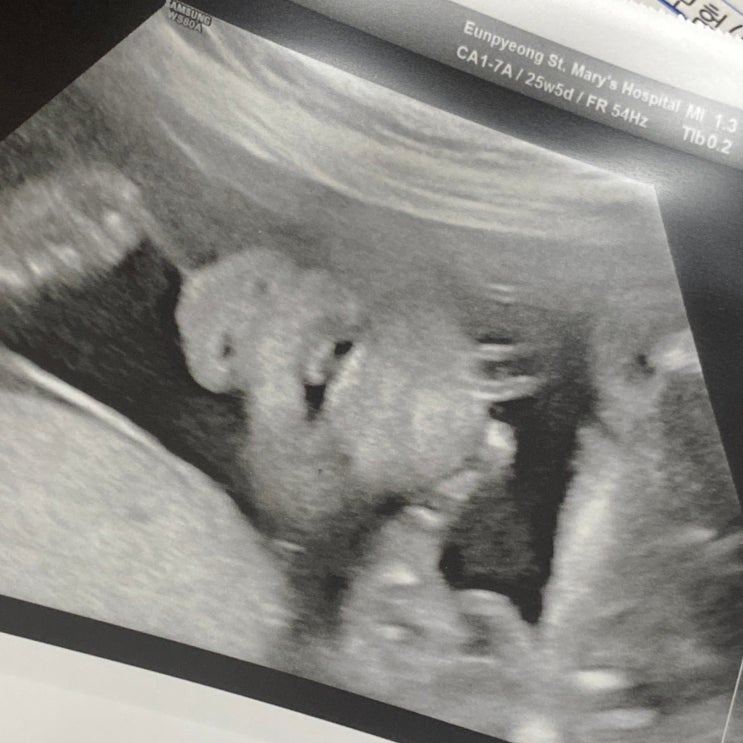

임신 25주차 임산부 임당검사 후기 / 25주 초음파사진( 은평성모병원 임당검사)

25주 5일차 / 임당검사 드디어! 5주만에 병원 당근이보러 병원가는날 진료예약시간은 오후 2시 점심시간 이...